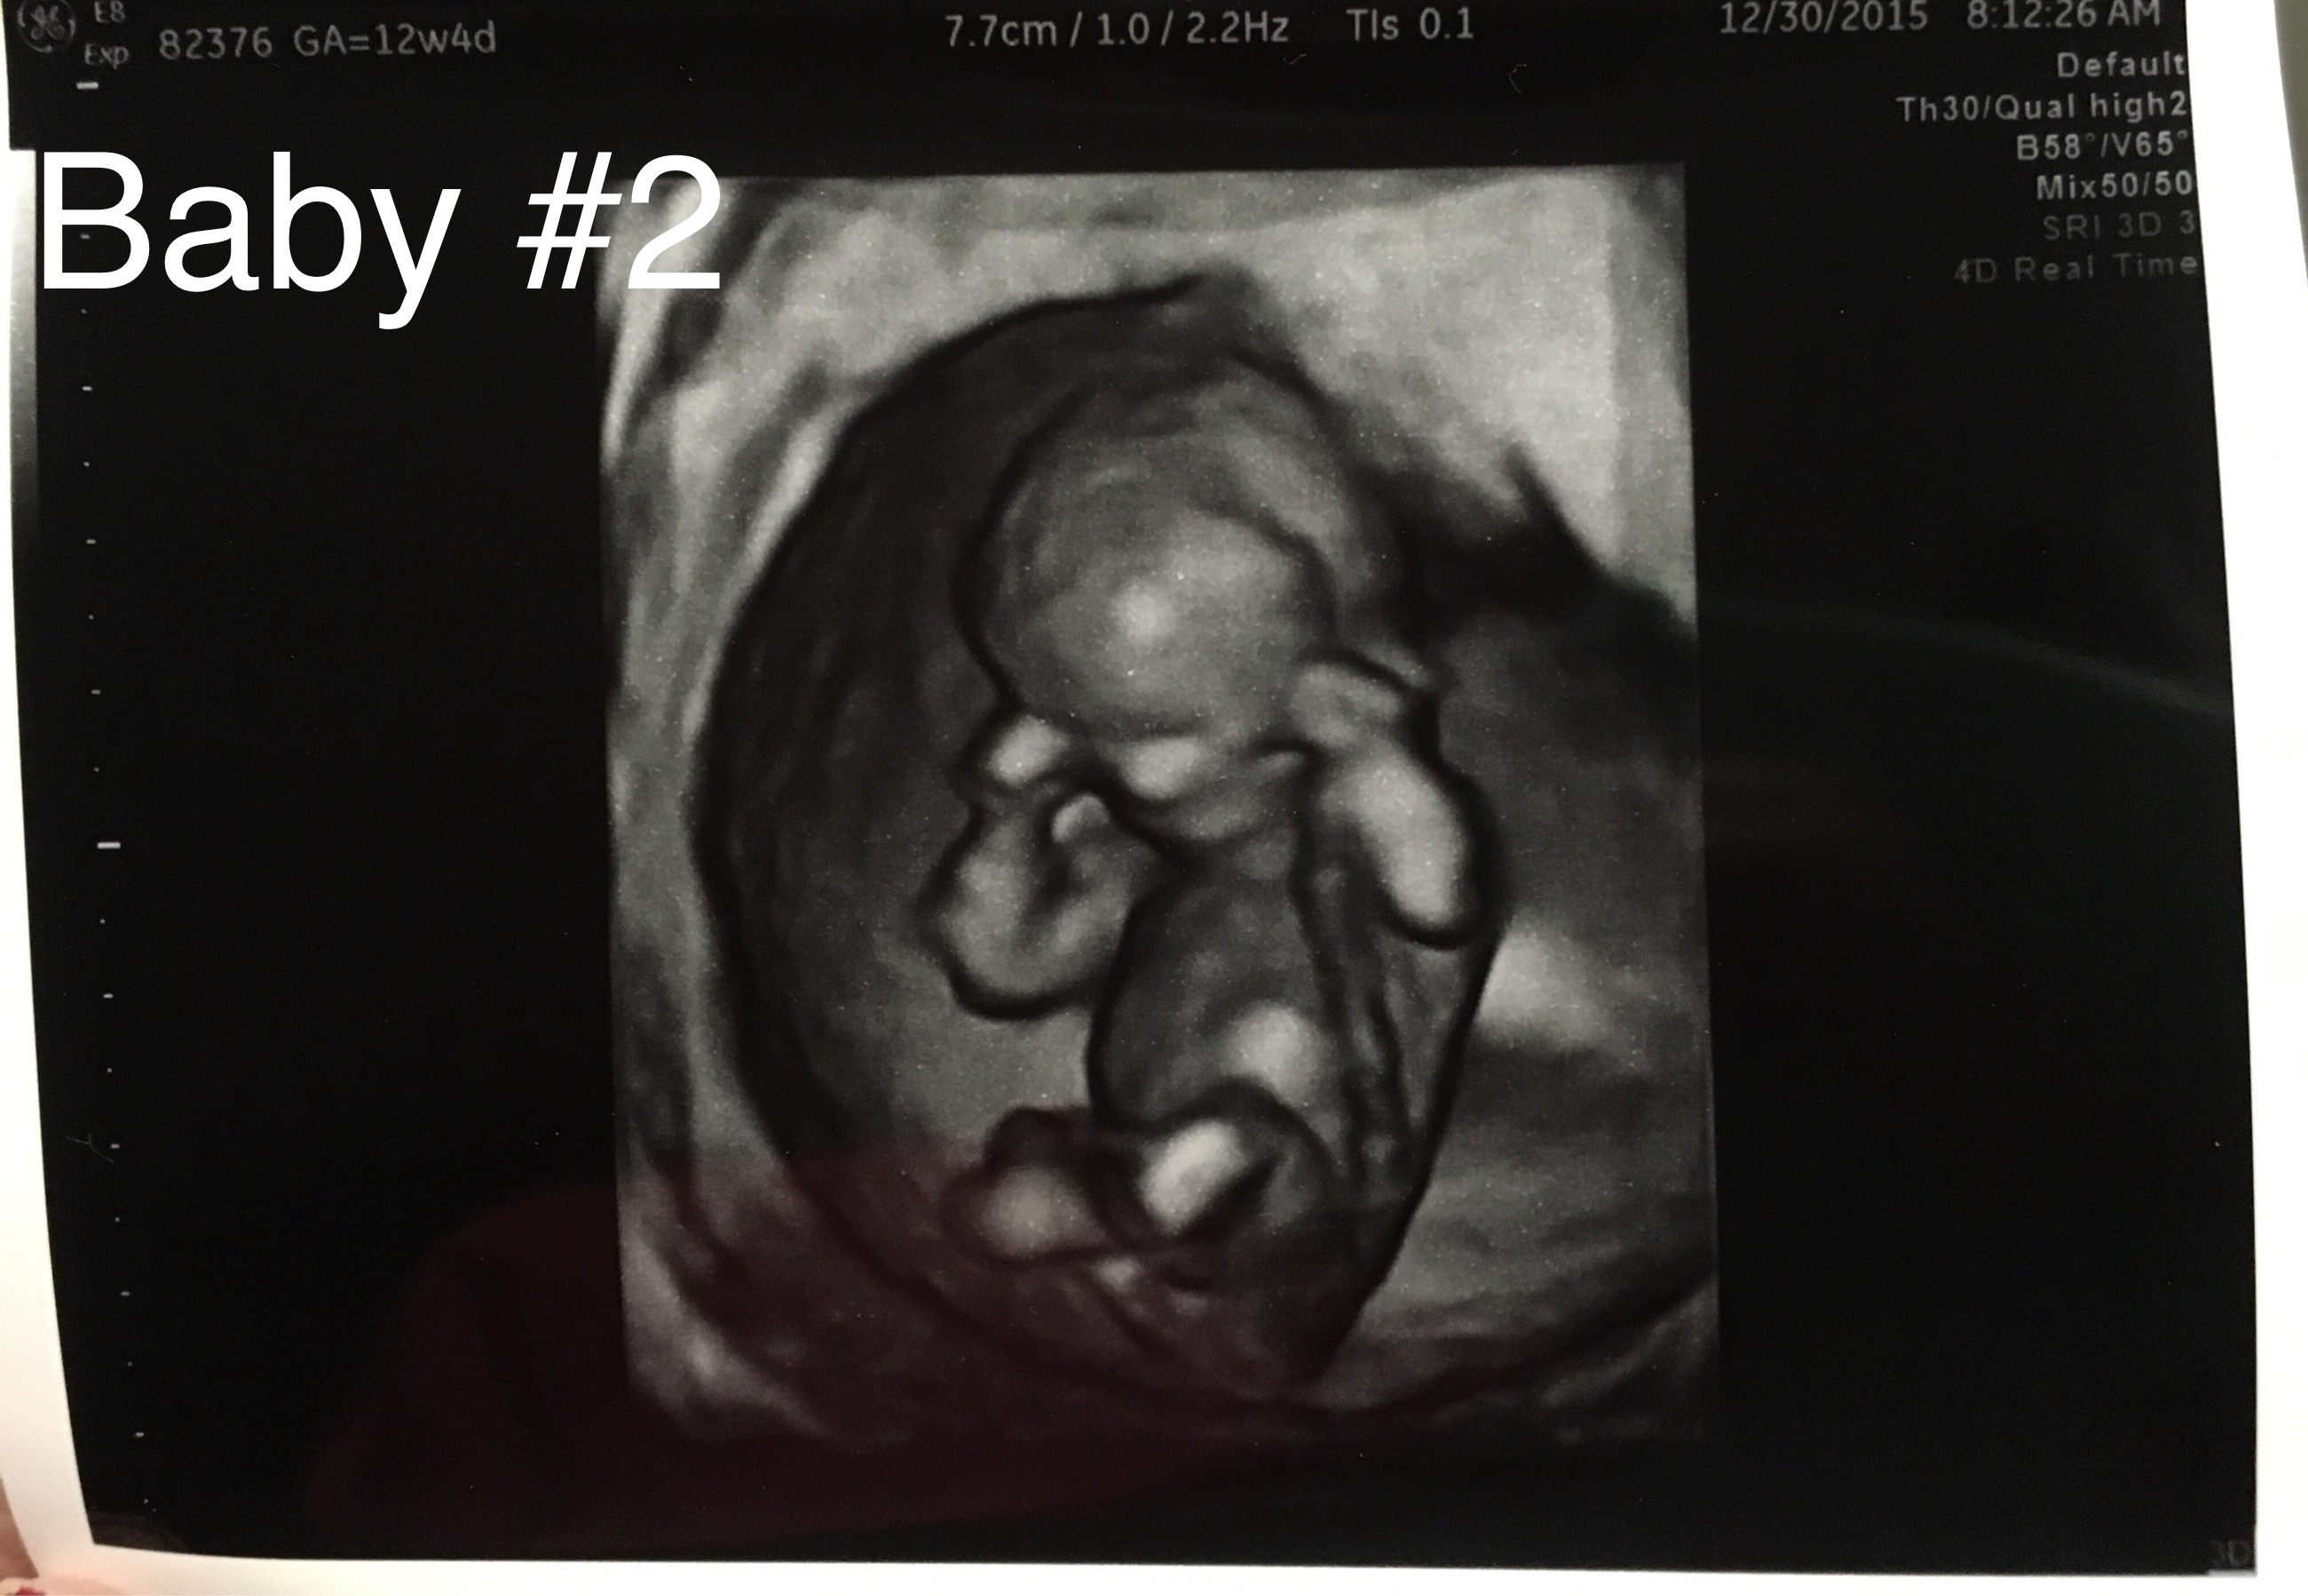

Below are my 12+4 week scan shots, I'm hoping for some gender guesses. Is the nub even visible? I've looked at tons of pics online and can't seem to make out the nub in my pic. I'm kind of thinking boy, this bub looks so much like my DS around the same time (in regards to skull shape, although this baby has a flatter face). I've attached pics of DS as well.

Here is current baby:

Attachment 29171